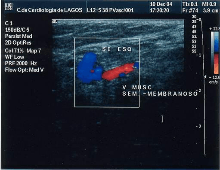

The small saphenous vein (SSV), runs along the posterior aspect of the leg as far as the popliteal region, in the upper calf. Here it enters the popliteal space which is located between the two heads of the gastrocnemius muscle where it usually drains above the knee joint in the popliteal vein or a little less often in the great saphenous vein (GSV) or other deep muscular veins of the thigh.[52] The use of ultrasonography has allowed a number of variations to be shown at this level; when no contact is made with the popliteal vein it might be seen to drain in the GSV, at a variable level; or, it may merge with the Giacomini vein and drain in the GSV at the superior 1/3 of the thigh. It can also but rarely, drain in the vein of the semimembranosus (thigh muscle) (shown below). Usually though, it connects with a perforator vein at its middle 1/3.[22] To check for insufficiency, the Paraná maneuver is very useful.[35]

![]() Insufficiency from the SSV flooded by the vein of the semimembranosus muscle |

![]() SSV variant draining in the vein of the semimembranosus muscle |